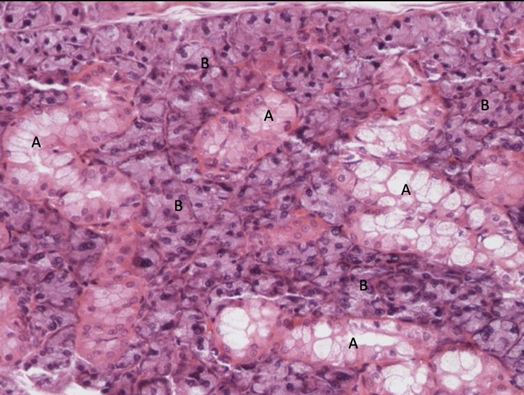

komórki pęcherzykowe = nabłonek jednowarstwowy sześcienny

koloid

komórki C

tarczyca (f. gruczołowa endokrynna nabłonka) nr 408

wyspa trzustkowa - wyspy Langerhansa

pęcherzyki trzustkowe